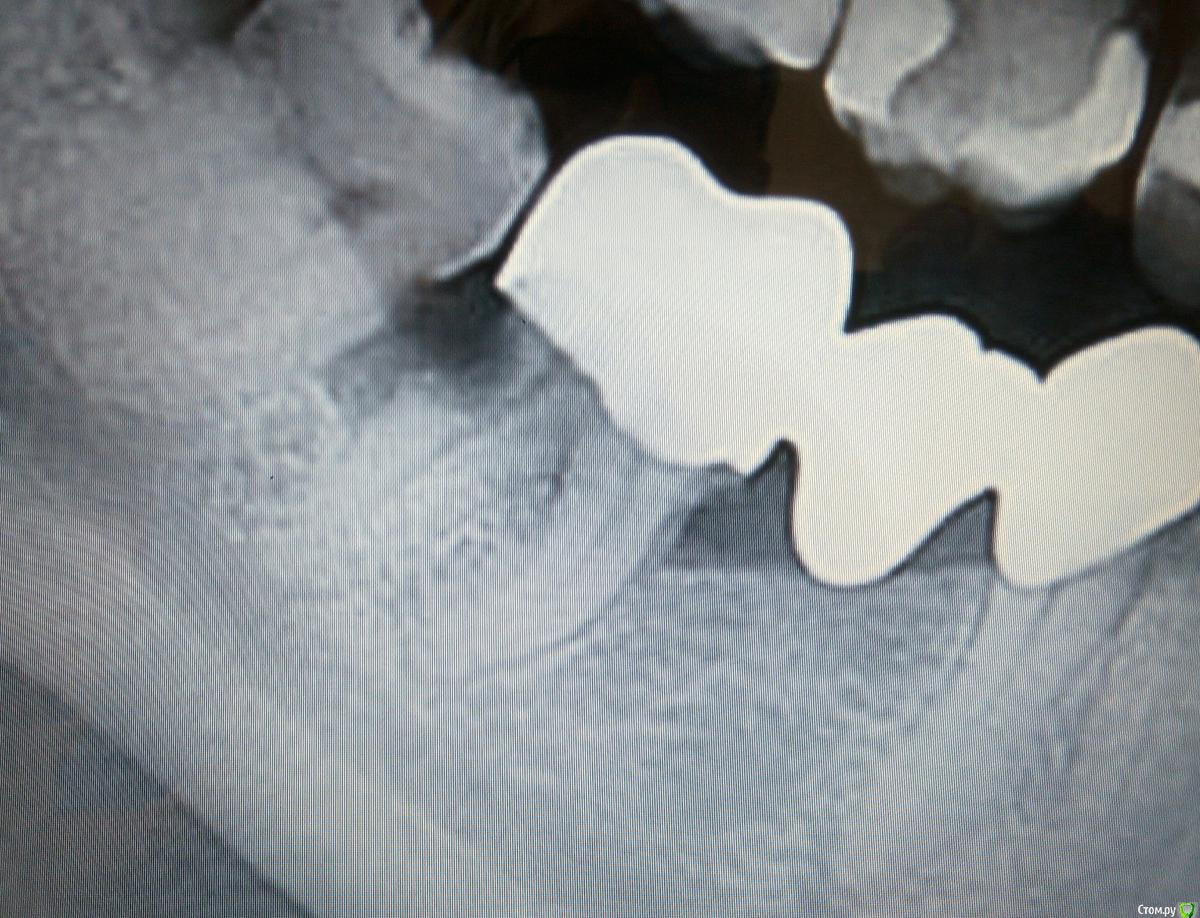

igorstom Опубликовано 23 ноября, 2019 Поделиться Опубликовано 23 ноября, 2019 Доброго времени суток! Далеко не редкость, когда у пациентов кариес цемента корня. Давайте поделимся своими соображениями по этому поводу. В теме будут рентгеновские снимки некоторых моих работ по данной тематике. В том числе и в отдаленные сроки.Начну со следующего сложного клинического случая, который был буквально пару месяцев назад. Пациент обратился с жалобами на периодические ноющие боли в зубе нижней челюсти справа, предполагает что причинный зуб под коронками. Была сделана ОПТГ. Результат четко виден. Какие соображения будут по этому поводу? Ссылка на комментарий

igorstom Опубликовано 23 ноября, 2019 Автор Поделиться Опубликовано 23 ноября, 2019 Удаление.1. Кариес корня это абсолютное показание к удалению. Это по стандарту, который в России законадательно не утверждён. Я не стал удалять весь зуб. Провел под коффером эндо-лечение медиальных каналов. Потом сделал короно-радикулярную сепарацию. Удалил дистальный корень. Далее провёл протезирование. Очень жаль, что многие почему-то не делают данную процедуру. А ведь ничего сложного нет. С 1997 года практикую. Тьфу-тьфу, проблем не было. Но только на нижних зубах. На верхних ни разу не проводил.Немного позже выложу рентген пациентки, которая лечилась у меня с менее глубоко расположенным кариесом цемента корня, чем у представленного выше пациента. Покажу результаты через 3 года. Кстати, эта пациентка переехала на ПМЖ в Санкт-Петербург, и по моему совету, когда её прихватила там нужда с зубами, пошла в клинику Доброго Стоматолога. Так что мои работы там видели, а я соответственно через некоторое время увидел их работы. ))) 5 Ссылка на комментарий